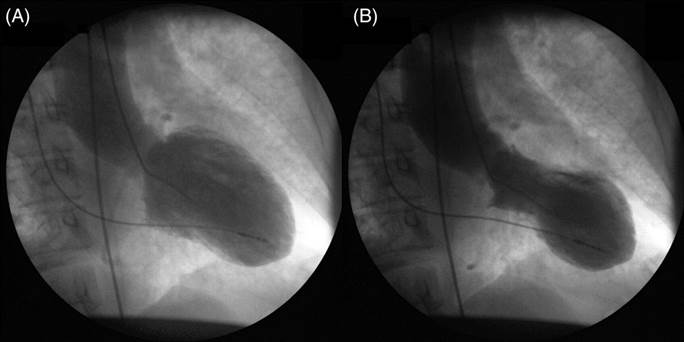

在這項小規模研究中,英國阿伯丁大學(University of Aberdeen)的研究員對52名心碎症候群患者進行了檢查。超聲波檢測和心臟磁共振成像顯示,這種症狀永久性影響了心臟的功能,心肌的扭動和收縮動作都明顯變慢。

部分心肌被細小的傷疤組織取代,因而降低了心肌的彈性,使心臟無法正常收縮。這也解釋了為何心碎症候群患者的長期存活率與心臟病患者相似。

研究的領導作者、阿伯丁大學的Dana Dawson博士說,以前人們認為無需醫學干預,心碎症候群患者亦可以完全自行恢復。然而,這項研究表明,心碎症候群對心臟的傷害更為持久。

僅靠時間,難癒心傷

英國心臟基金會的醫學副主管Metin Avkiran教授對這一結果表示擔憂:「一些心碎症候群患者,即使在患病四個月後,他們心臟功能的多個方面仍然不正常。讓人擔心的是,這些患者的心臟似乎出現傷疤,表示需要更長的時間才能完全康復,在現有醫療條件下,甚至有可能無法完全康復。」